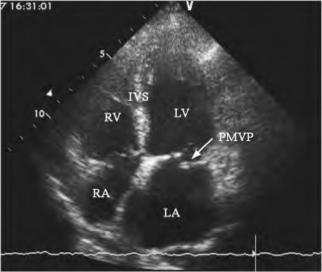

图13-10 二尖瓣后叶脱垂二维超声图

心尖四腔切面,显示收缩期二尖瓣后叶脱入左房(箭头所示)